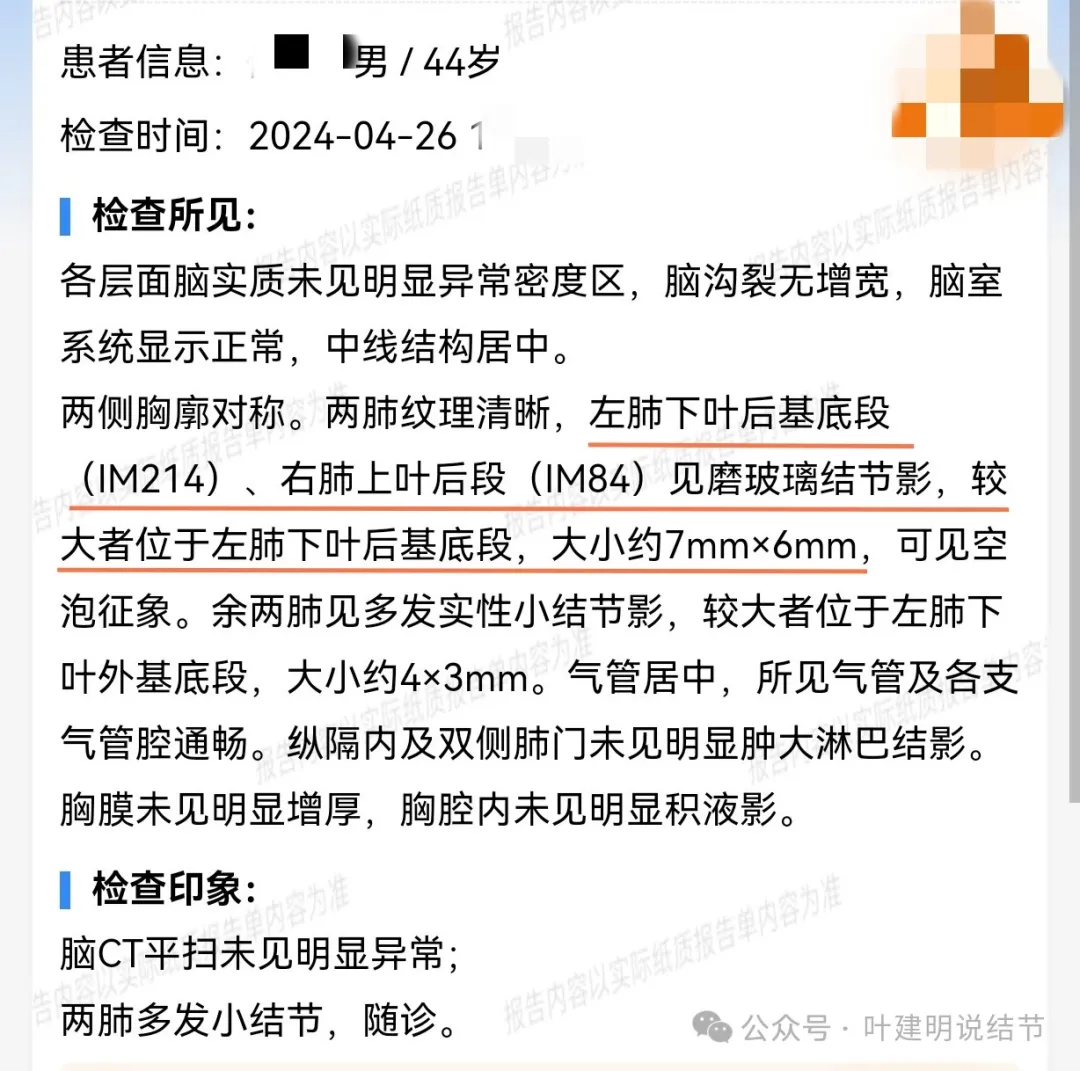

男性, 44岁 。

查体发现肺结节1个月余。

患者于1个月余前查体发现肺结节,无发热,无胸痛胸闷,无头晕头痛,无腹痛腹胀,于2024.04.26就诊于医院行胸部CT检查示脑两肺多发磨玻璃结节,左下肺后基底段达Lung-rads4B类,微浸润腺癌可能,建议手术干预。今为求进一步诊疗来诊。

在影联网问了本省胸科医院。

上图是当地的影像报告,印象是两肺多发小结节,随诊。这很非常正常,也是合理的。结果骚操作来了!请该省级胸科医院教授会诊!下面是会诊时的意见:

某省胸科医院医生会诊后给出的意见是:左下肺后基底段(结节)达Lung-rads4B类,微浸润性腺癌可能,建议手术干预。签名的是B医生,后面给出了周一A主任肺结节门诊,周四B主任门诊。大概是团队成员,A医生是著名大咖,B医生是团队骨干成员!